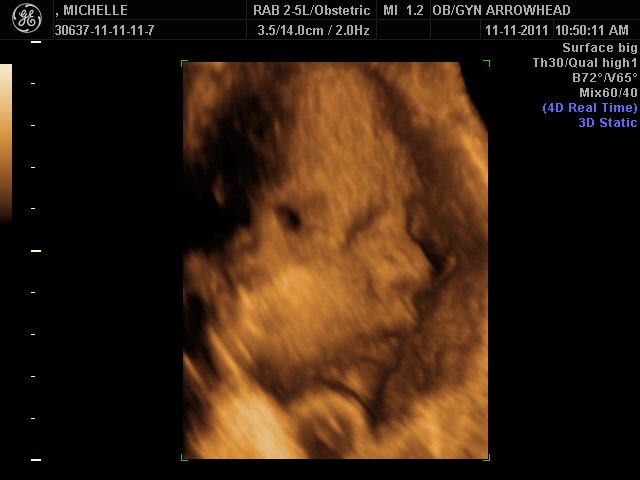

We offer complimentary 3D/4D Ultrasounds to all our OB patients around 30 weeks! The following photos are some examples of our work, shown with permission from our patients.